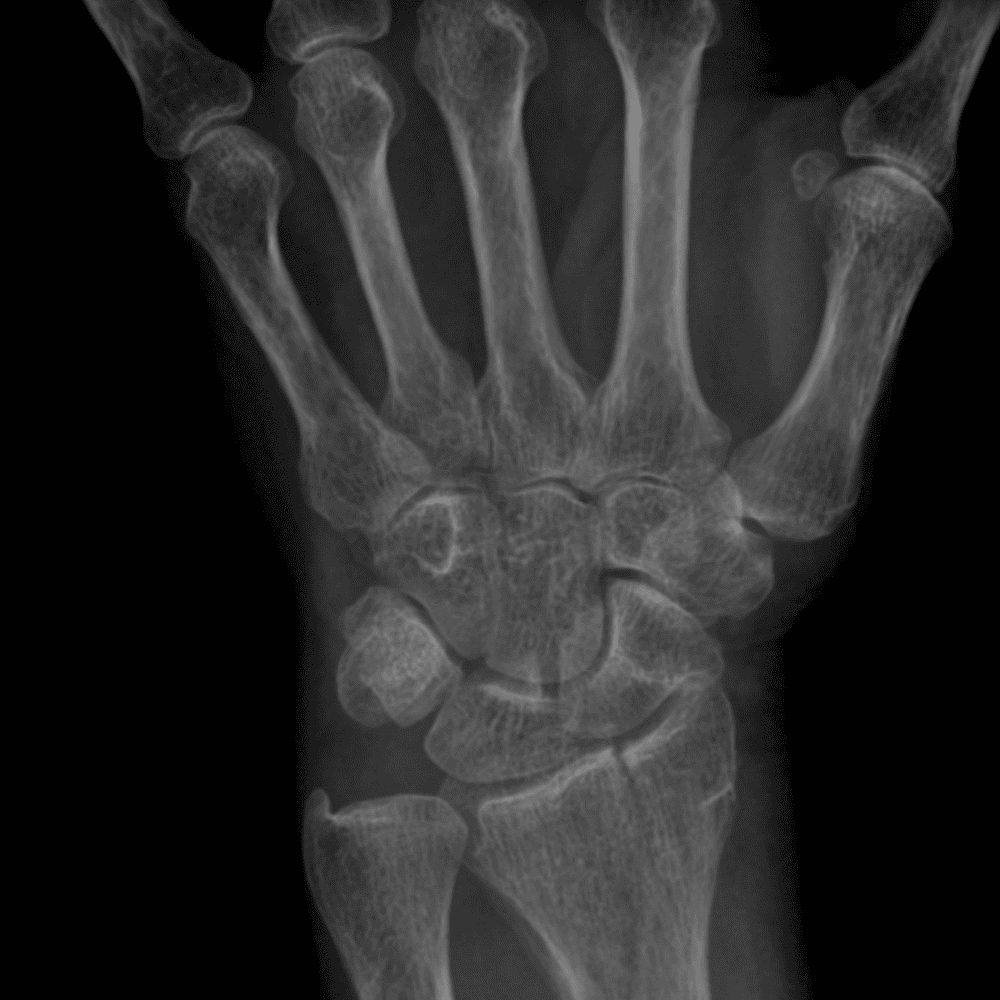

Simuliert den Dienst durch subtile oder schwierige Fälle und einige Normalbefunde.

30 Fälle